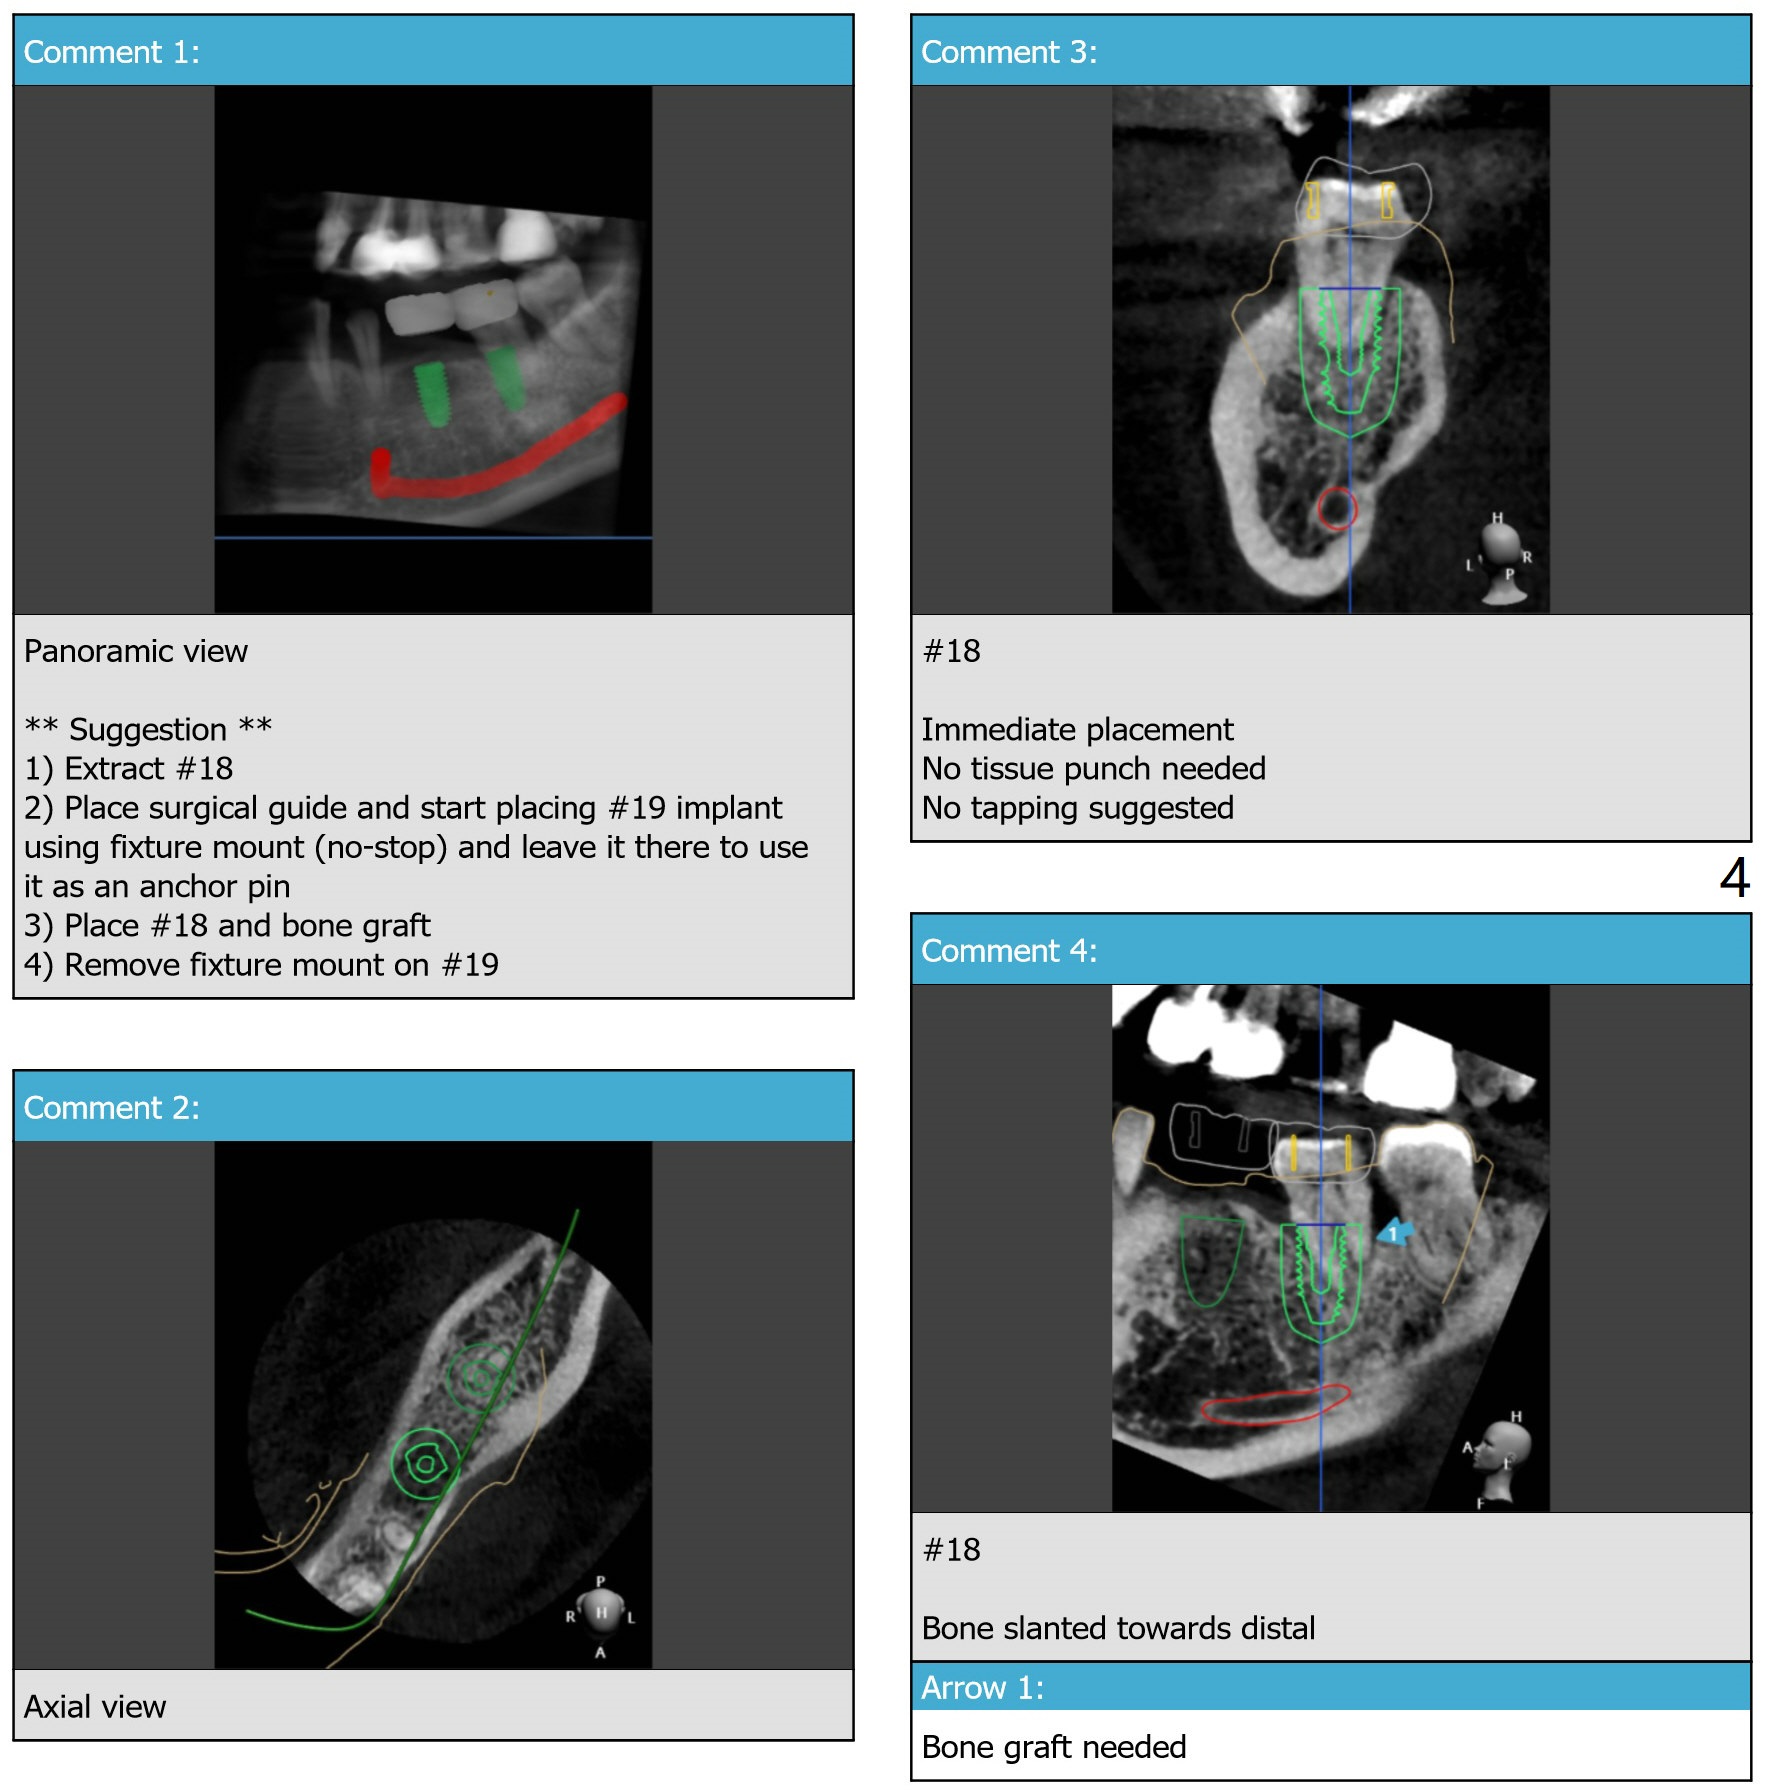

A 46-year-old woman

Molar Immediate Implant,

Prevent Molar Periimplantitis (Protocols,

Table),

Trajectory II,

No Deviation,

No Antibiotic